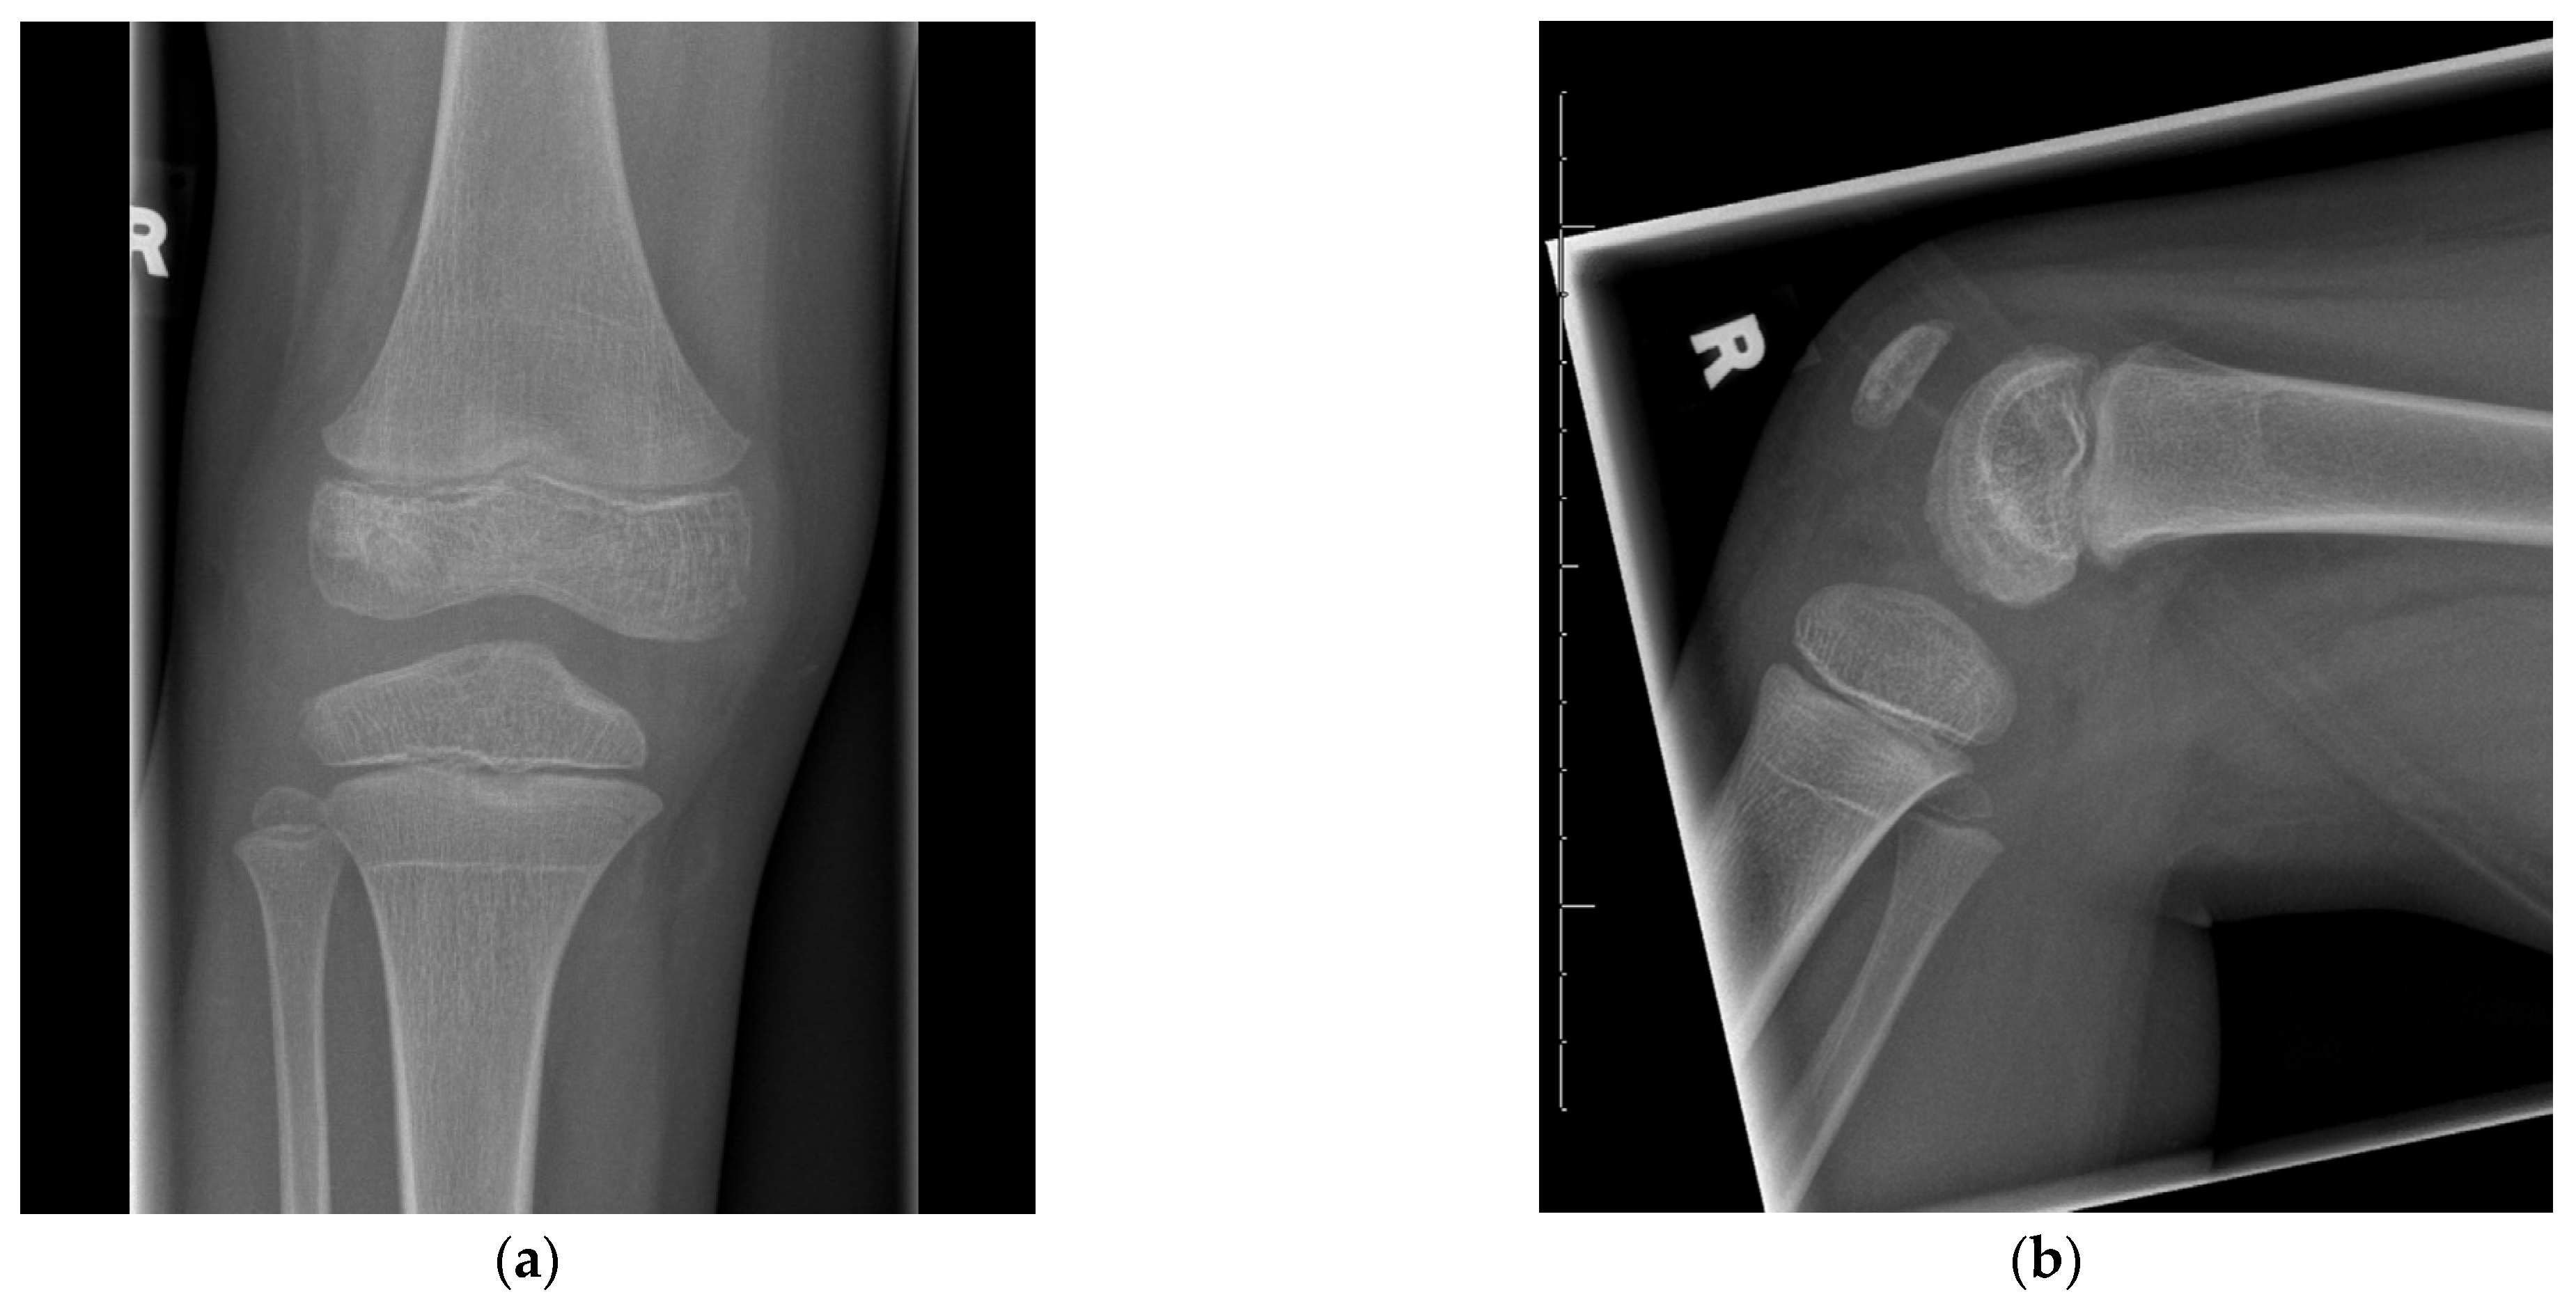

Surgical Management of an Osteomyelitis Associated Subchondral Bone Defect in the Pediatric Knee Based on Arthroscopy, “Ossoscopy” and Bone Grafting—A Case Report

2. Case Presentation